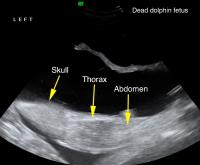

Y37 fetus ultrasound. Reproductive ultrasound image of dolphin Y37 showing an approximately 18-week gestational age fetus in a longitudinal plane, acquired in August of 2011. Dotted line shows the skull biparietal diameter, which is used to estimate gestational age and parturition date. Boat-based surveys documented that the pregnancy was successful. Dolphin Y37 was seen with a live calf in both April and August of 2012.

Dr. Cynthia Smith, National Marine Mammal Foundation